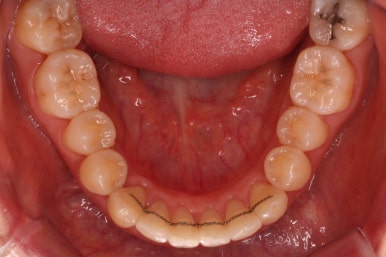

부산설측교정 키다리아저씨치과에서 부분교정을 마무리 하였습니다.

장치를 모두 제거하고 유지철사를 안쪽으로 부착하고 치료를 종료하였습니다.

전후사진을 비교해 보겠습니다.

삐뚤었던 부위들은 가지런하게 정리가 되었습니다.